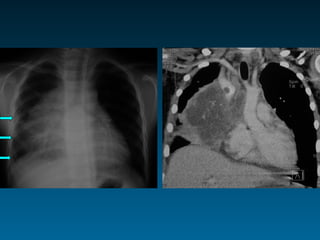

• #3 Συστηματική προσέγγιση